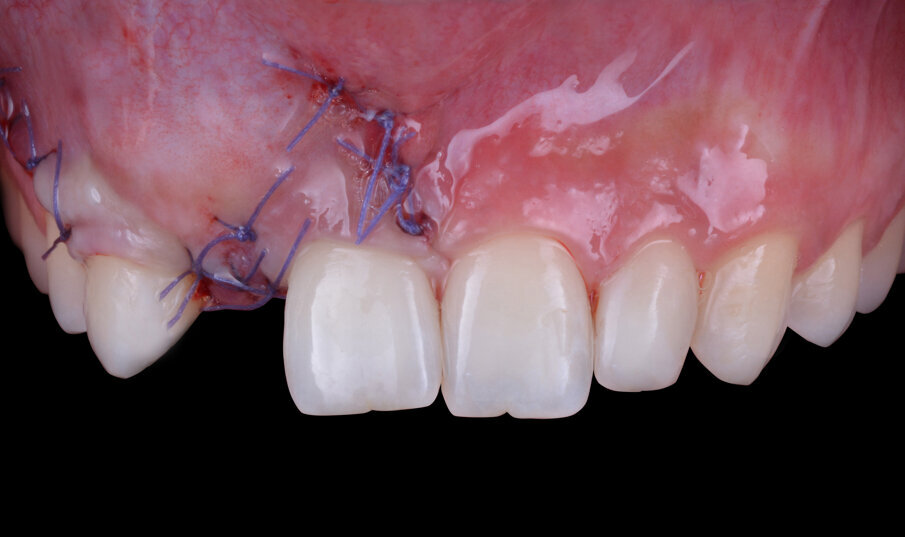

Ad inserimento della fixture avvenuto si rileva la presenza di una piccola fenestrazione vestibolare classificabile come un’atrofia vestibolare di Classe II secondo la classificazione di Chiapasco e Casentini dei difetti ossei perimplantari del 20188 (Fig. 6). La tecnica chirurgica scelta per la gestione del difetto osseo è la GBR. Il primo step contempla di eseguire dei fori di osteopromozione sulla corticale vestibolare attraverso uno strumento rotante a basso numero di giri e senza ausilio di irrigazione con acqua fisiologica così da ottenere un maggior apporto ematico endostale nella regione da trattare e la successiva aggiunta di particolato di osso autologo che conferisca osteoinduttività e osteogeneticità all’innesto (Fig. 7). Il difetto viene gestito impiegando scaffold inorganici, ovvero dei biomateriali che fungono da riempitivi inerti con proprietà osteoconduttive (in grado di guidare la rigenerazione ossea facilitando la stratificazione e l’organizzazione del coagulo su di essi) e di space making (capaci di mantenere lo spazio necessario alla rigenerazione impedendo il collasso parziale o totale dei tessuti molli sovrastanti)9. Nel caso specifico, il biomateriale eterologo innestato è di origine bovina (Nobel Biocare Xenogain 0,2-1 mm); dopo l’accurato posizionamento del biomateriale nella regione da trattare si procede alla protezione dello stesso con una membrana riassorbibile in pericardio bovino con matrice tridimensionale (Ubgen, Shelter/sistema Pericross) stabilizzata per mezzo di pins di fissazione sia palatalmente che vestibolarmente (Fig. 8). L’esecuzione di un’incisione di rilascio periostale del lembo vestibolare permette di ottenere una chiusura per prima intenzione della ferita caratterizzata da una competente interfaccia dei due lembi e da una passivazione degli stessi (Fig. 9). La dimissione della paziente avviene solo dopo aver applicato con cementazione adesiva il Maryland bridge provvisorio prestando particolarmente attenzione a evitare compressioni sui tessuti molli appena trattati chirurgicamente. Durante il periodo di guarigione la paziente viene rivalutata con cadenza mensile per controllare il procedere del fisiologico decorso post-operatorio. A 6 mesi dall’inserimento dell’impianto, dopo opportuni controlli radiografici, si procede con la programmazione della riapertura.

Fig. 9 - Chiusura della ferita per prima intenzione.